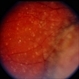

Choroidal Melanoma With Vitreous Seeding

Choroidal Melanoma

Underlying retinal choroidal melanoma with dense vitreous seeding of choroidal melanoma cells.